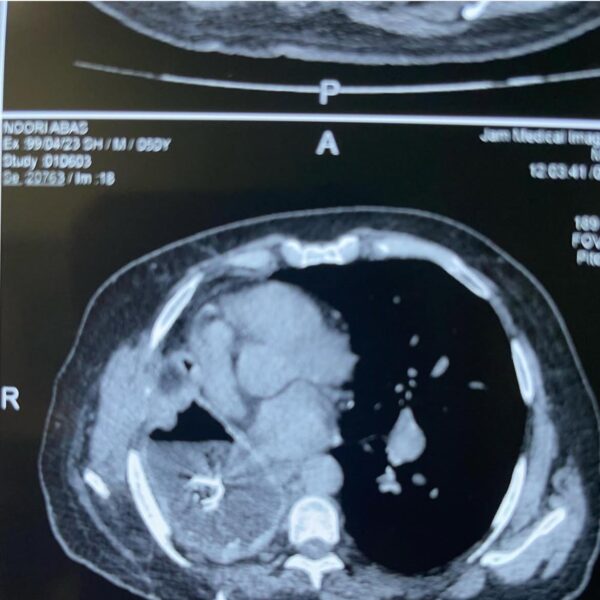

توضیح: اولین عمل موفقیتآمیز پیوند ریه در مجتمع بیمارستانی امام خمینی بعد از پاندمی کرونا